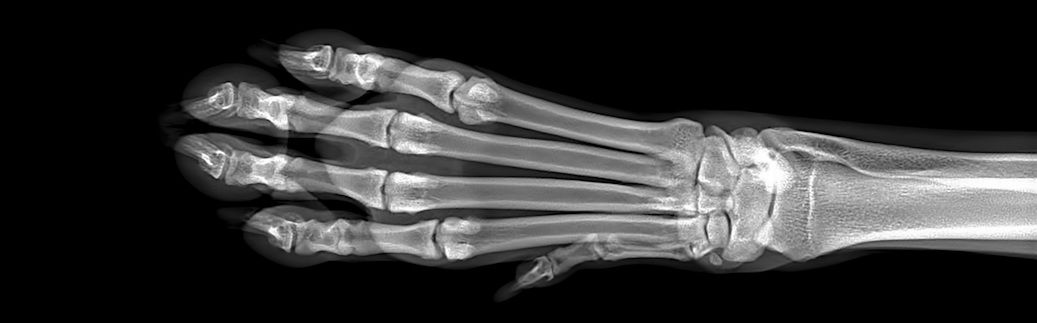

- Identifying and evaluating broken bones, fractures, or bone deformations

- Diagnosing hip dysplasia, elbow dysplasia, and other orthopedic issues

Vets often use x-rays to diagnose health problems, and they may use them to monitor your dog’s progress as they heal from a fracture or other problem. X-rays are fast and painless, and since they provide instant results, they’re helpful for many different situations, especially in emergencies.

X-rays use electromagnetic waves to create pictures of your dog’s organs, muscles, blood vessels, and bones. But x-rays don’t reveal everything, and they aren’t right for every scenario.

An x-ray doesn’t display every material well, including some plastics and even tumors, which can blend in with the appearance of other tissue on the film. X-rays also don’t provide very clear images of certain parts of the body—including your dog’s brain, inner heart, lungs, bladder, or some abdominal organs.